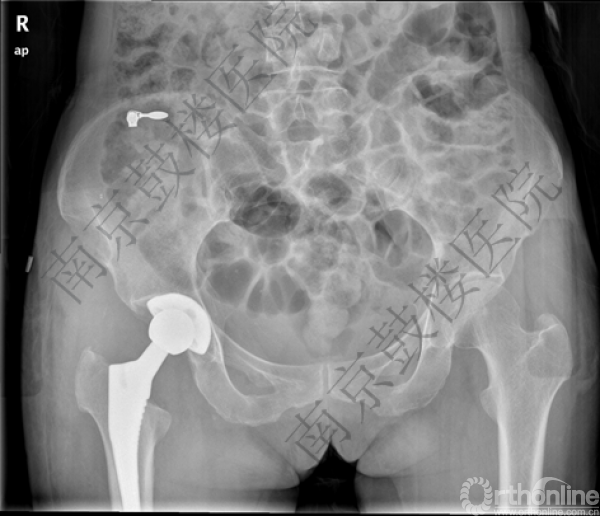

2015年8月28日,南京鼓楼医院翁文杰教授为现年64岁的李女士顺利进行了前入路小切口(DAA)全髋关节置换术,患者手术后第二天即可下地行走并无需使用辅助器械,取得了良好的效果。这已是翁文杰教授团队进行的又一例DAA全髋关节置换术,成为江苏省首家掌握该技术的医疗团队。

全髋关节置换术是治疗终末期髋关节疾病的重要手段,传统的各种手术入路均需要切断部分肌肉,患者术后需要较长的时间恢复正常步态,部分患者甚至可能残留步态异常。DAA入路是目前全髋关节置换术中唯一真正意义上的神经肌肉界面入路,不损伤神经和肌肉,可令患者获得早期、快速康复。在美国,该技术已令超过20%髋关节置换的患者受益,是目前开展最广泛的微创全髋关节置换手术。

手术图片